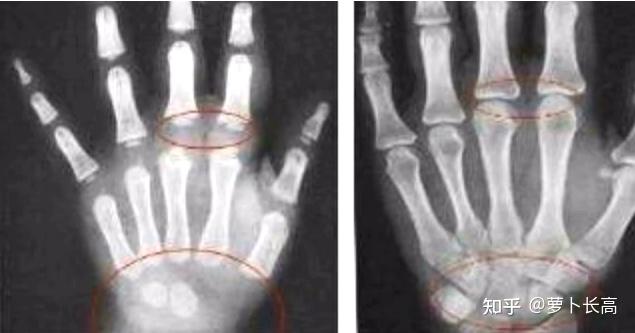

比尔高真的能够长高吗?会不会反弹?

1、据广大用户反映,康恩贝比尔高能够有效促进孩子的生长发育,官方数据统计,不同体质的孩子服用比尔高一疗程,均可以长高36公分,而且没有任何副作用这主要得益于比尔高特含的助长因子,如丰富的赖氨酸和磷酸氢钙赖氨酸是人体必...